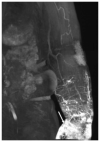

Background: Clinical examination and lymphoscintigraphy are the current standard for investigating lymphatic function. Magnetic resonance imaging (MRI) facilitates three-dimensional (3D), nonionizing imaging of the lymphatic vasculature, including functional assessments of lymphatic flow, and may improve diagnosis and treatment planning in disease states such as lymphedema.

Results: From 612 identified articles, 43 articles were included and their protocols and results summarized. Field strength was 1.5 or 3.0 T in all studies, with 25/43 (58%) employing 3.0 T imaging. Most commonly, imaging of the peripheries, upper and lower limbs including the pelvis (32/43, 74%), and the trunk (10/43, 23%) is performed, including two studies covering both regions. Imaging protocols were heterogenous; however, T2 -weighted and contrast-enhanced T1 -weighted images are routinely acquired and demonstrate the lymphatic vasculature. Edema, vessel, quantity and morphology, and contrast uptake characteristics are commonly reported indicators of lymphatic dysfunction.